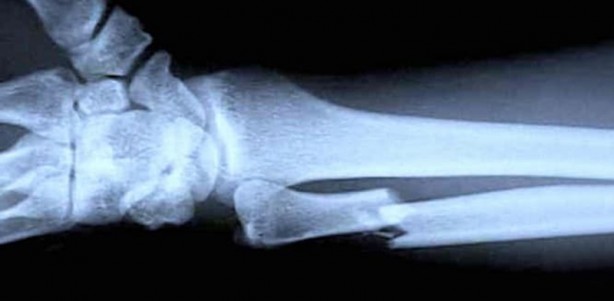

Bu hastalık kemik kırılması ve kemik erimesine yol açabilir.

Ortopedik problemler için mutlaka doktora görünmelisiniz.